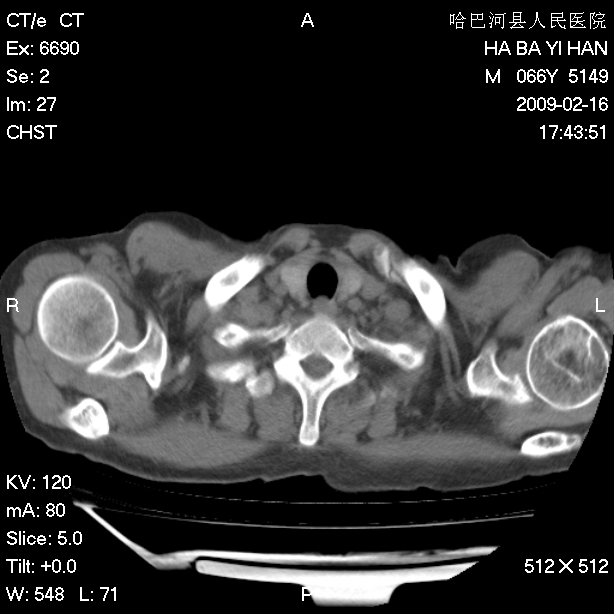

以下是引用huangxun4321在2009-2-16 20:18:00的发言:[br]部分病灶可见硬化边,部分可见骨质破坏消失,部分病灶内可见骨脊,说明病灶内既有良性病变,又有恶性病变,考虑骨巨细胞瘤恶变,未除骨纤恶变,畸形性骨炎少见,亦要考虑.

以下是引用731208在2009-2-16 20:31:00的发言:[br]考虑恶性胸膜间皮瘤并肋骨,脊柱转移。

以下是引用yijiansheng在2009-2-16 20:16:00的发言:[br]考虑恶性胸膜间皮瘤并肋骨,脊柱转移。

以下是引用形影不离在2009-2-16 19:55:00的发言:[br]考虑多发性转移瘤。